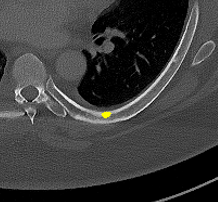

Figure 2: Qualitative results of bone lesion detection. Each column shows a cropped slice with the top row displaying ground-truth (green) and the bottom row showing nnUNet predictions (yellow). (a) shows a TP osteolytic lesion; (b) shows the prediction of a real osteoblastic lesion that was not prospectively marked as ground-truth (before review), and after GT review, it was correctly considered as ground-truth; (c) shows an osteolytic lesion not annotated in ground-truth before review and correctly marked afterwards. A FN adjacent to it is also shown. (d) shows a rare FP on the cortex of a rib.

Results. Qualitative and quantitative results of our model are presented in Fig. 2 and Table 1 respectively. Our model achieved a precision of 96.7% and a recall of 47.3% for detection of bone lesions (lytic, blastic, and mixed). We observed that the model was very confident in its predictions as demonstrated by the vast number of actual lesion predictions (TPs) compared against the FPs. Despite the high precision, the model was not very sensitive to the detection of bone lesions due to the large number of FNs.